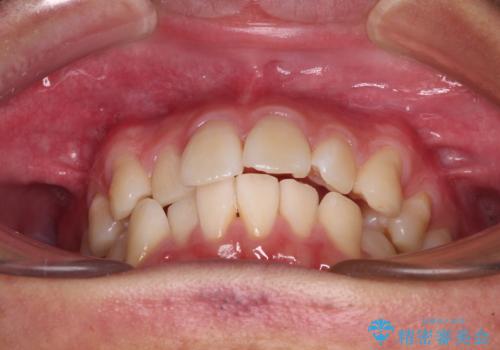

前歯のデコボコをインビザラインで綺麗に改善

- 上下前歯のデコボコとクロスバイトを気にして来院された患者様です。

インビザラインを用い、IPR(歯と歯の間を削る)と歯列全体を拡大させることで、歯並びを整えていくこととしました。